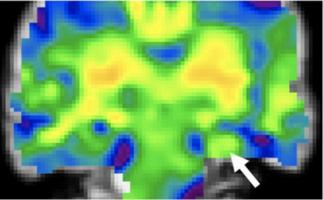

ÉPILEPSIE : L’IA détecte ses anomalies cérébrales sources

ÉPILEPSIE : L’ERM mieux que l'IRM ?